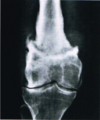

Fratura do platô tibial lateral - Schatzker tipo 2 (traço de fratura + depressão do plato lateral).